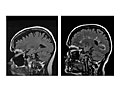

For an MRI of the head, you lie with your head inside a special machine (scanner) that has a strong magnet. The MRI can show tissue damage or disease, such as infection or inflammation, or a tumor, stroke, or seizure. Information from an MRI can be saved and stored on a computer for more study. Photographs or films of certain views can also be made.

During the test

During the test you will lie on your back on a table that is part of the MRI scanner. Your head, chest, and arms may be held with straps to help you lie still. The table will slide into the space with the magnet. A device called a coil may be placed over or wrapped around your head.